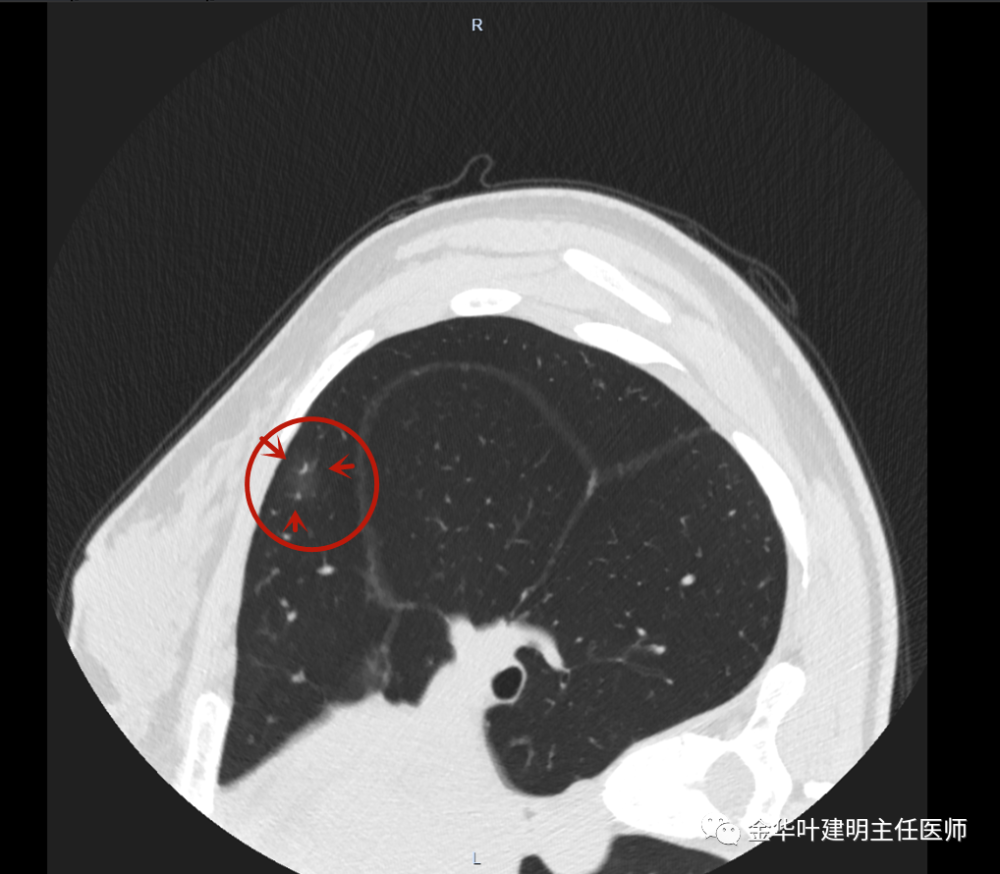

磨玻璃结节中有实性成分,我们称之为混合性磨玻璃结节,恶性概率相对最

发现这个小结节直径8mm,边缘比较模糊,是一个磨玻璃结节,没有明显的

见右上叶前段磨玻璃结节先来看平扫的图像:病人某a,于今年4月份在本院